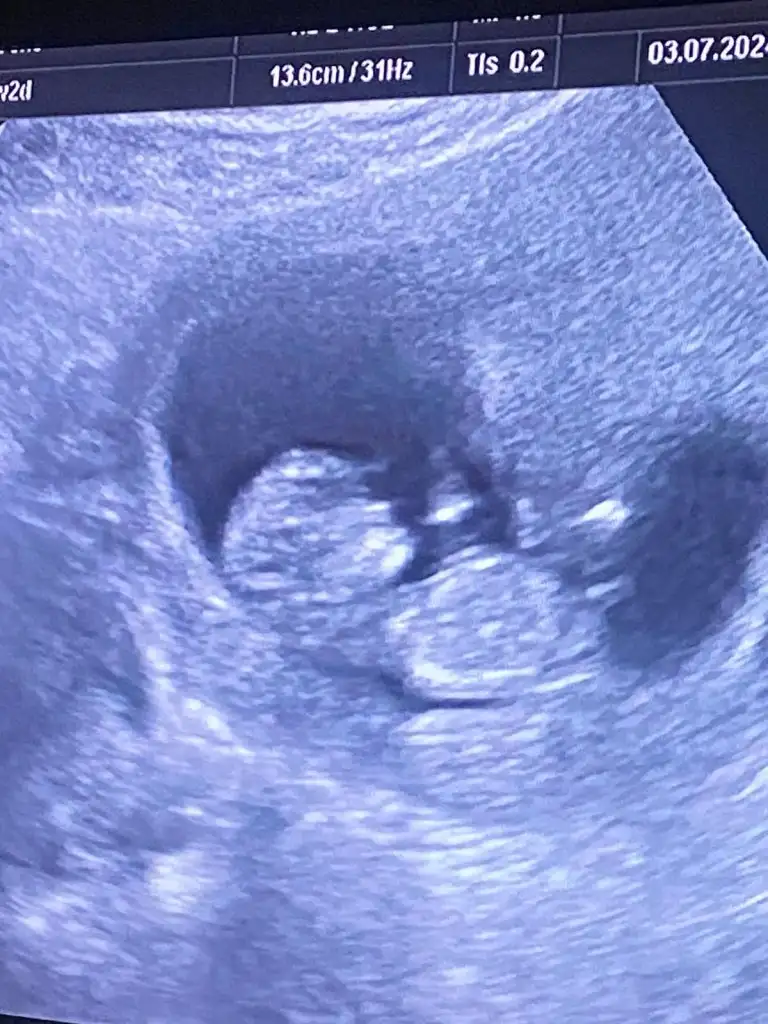

Yaaa kızlar ne güzel cinsiyetler öğrenilmeye başlanmış 😍😍 herkesin gönlündeki olsun inşallah ama önce sapsağlıklı olsun bebişlerimiz.. dün 10+5 de doktor bize yorum yapmadı. 12+0 da detaylı ultrason bakacağım o zaman bir tahmin yaparız dedi 🤭🤭 ama varsa bir yorumunuz yazabilirsiniz bize de 🤗

Erkek gibi geldi bana 🙈🫠